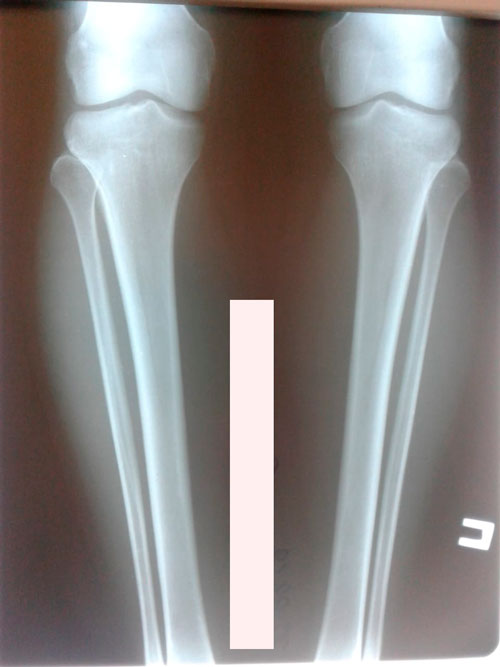

Исходник - 35 лет.

Дата операции - 29.04.2019г.